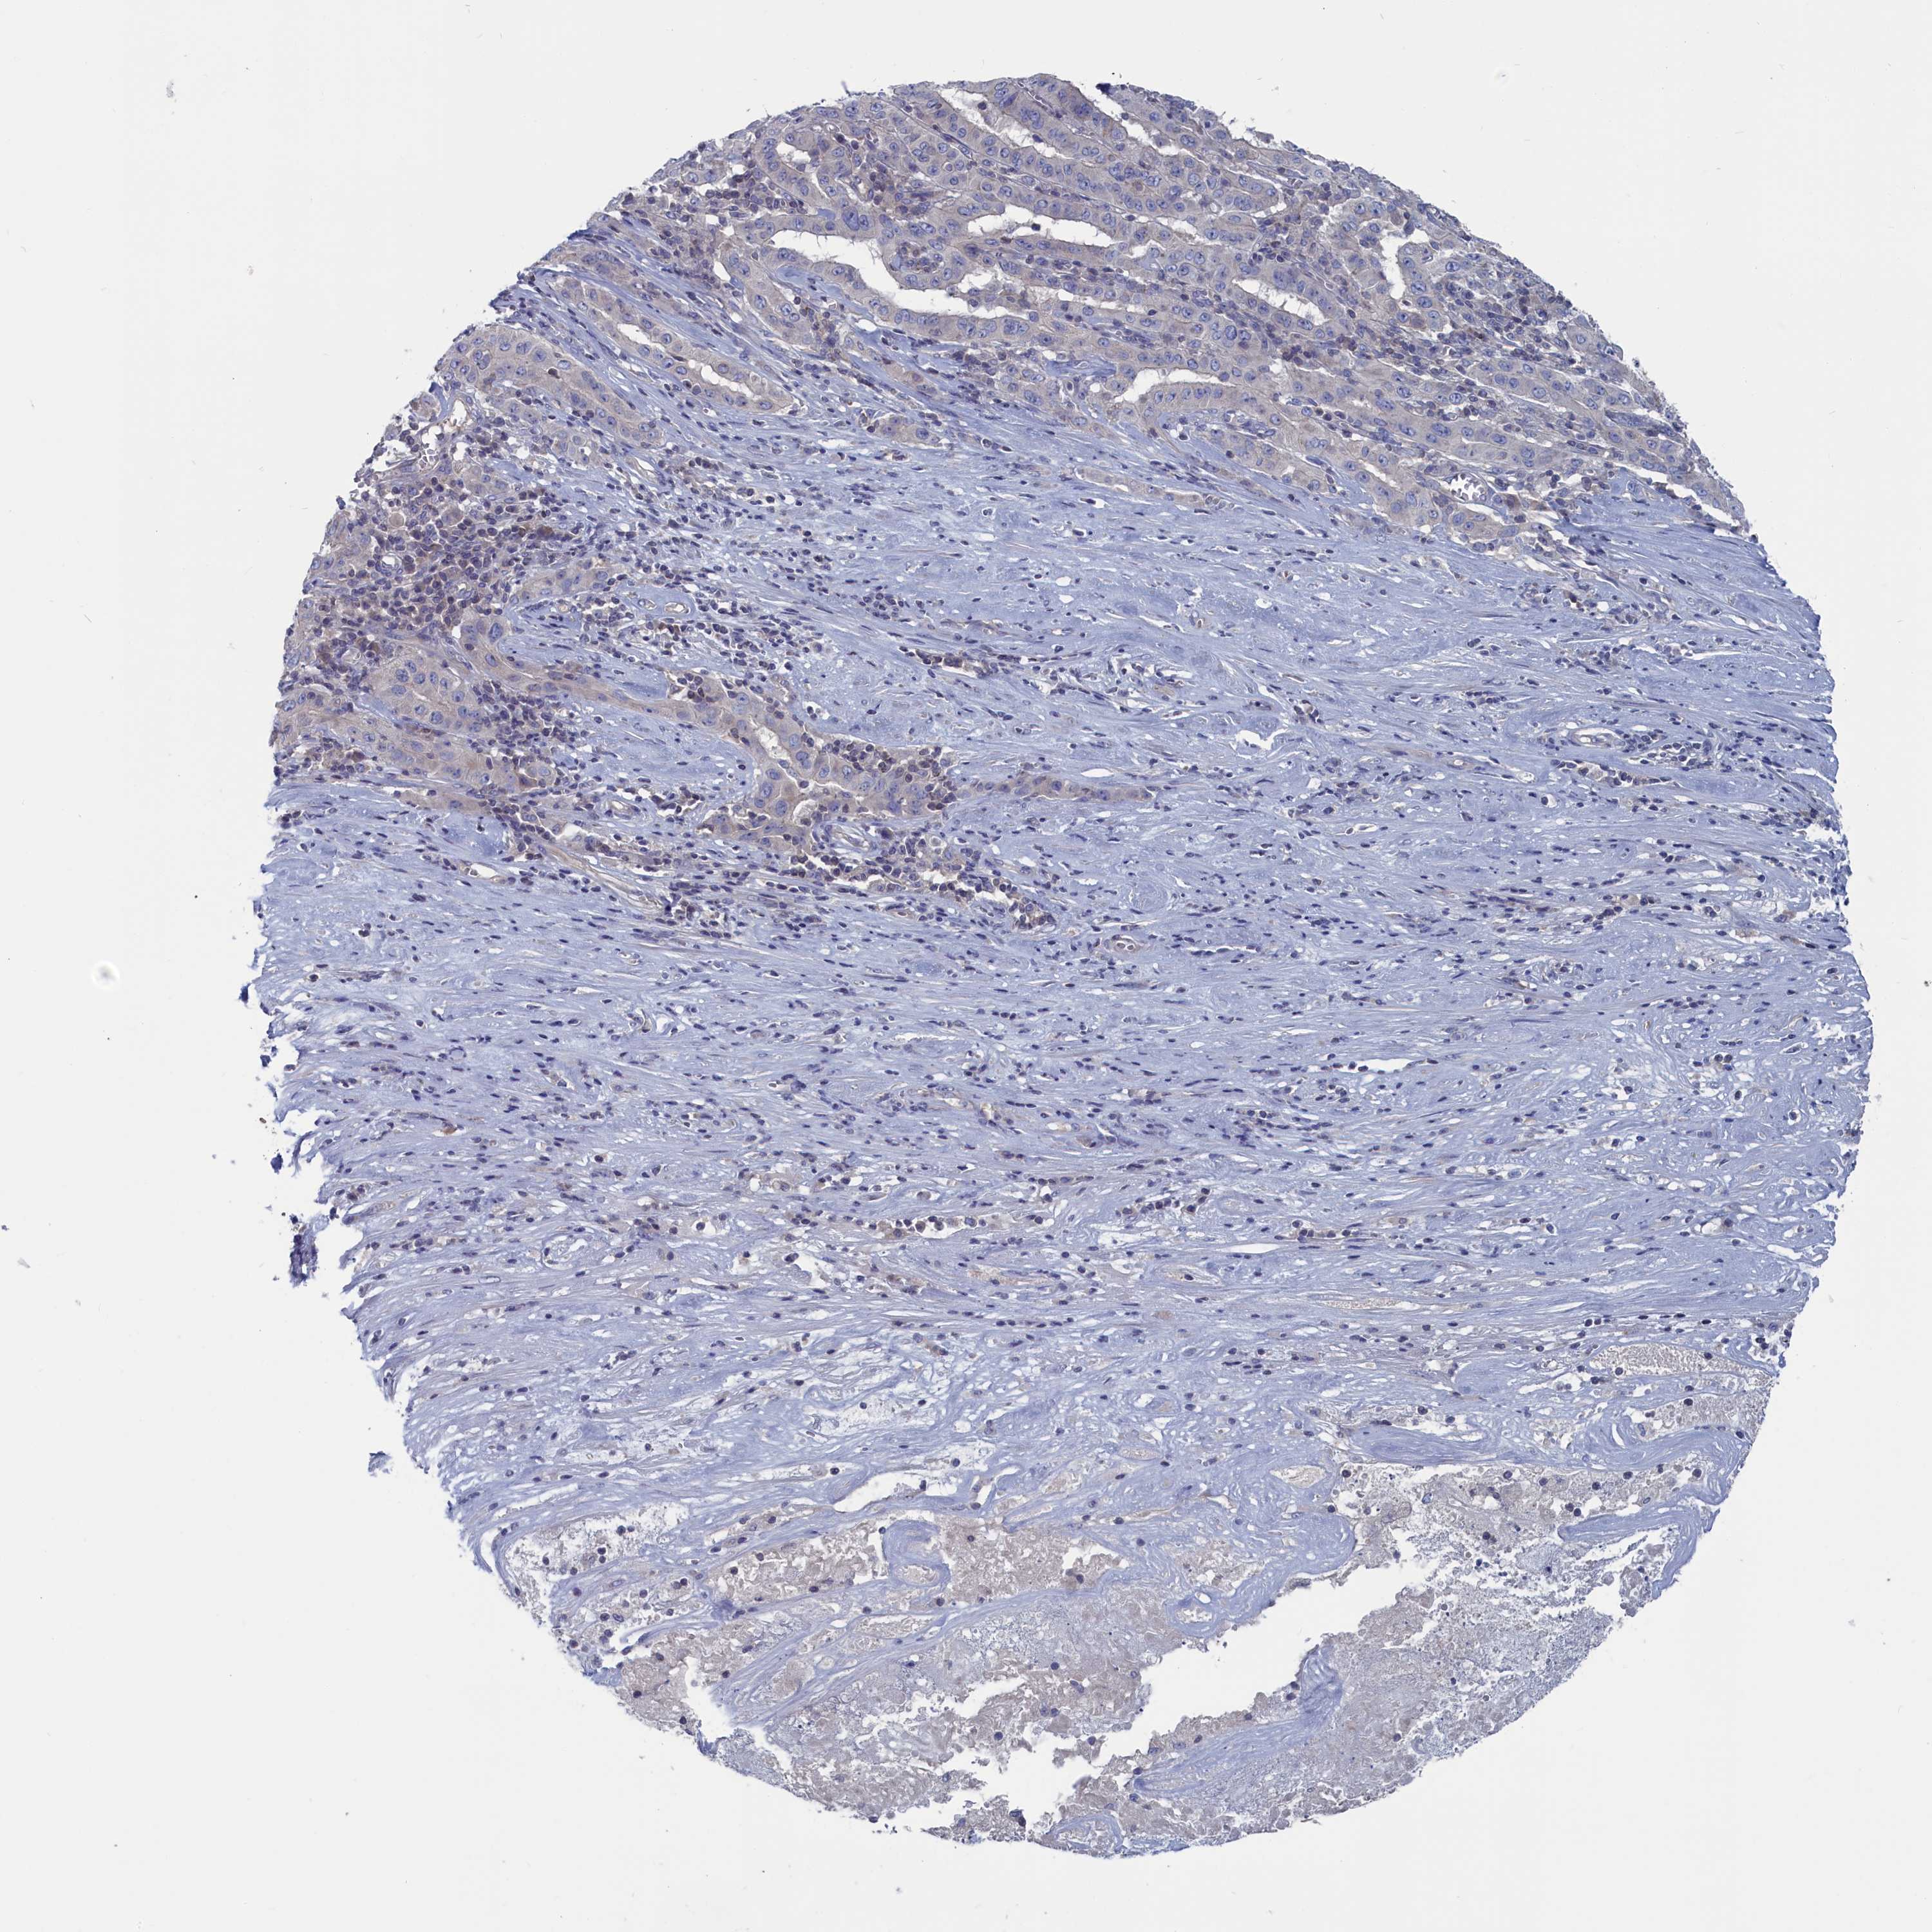

PANCREATIC CANCER - Protein expressioni

A mouse-over function shows sample information and annotation data. Click on an image to view it in a full screen mode. Samples can be filtered based on level of antibody staining by selecting one or several of the following categories: high, medium, low and not detected. The assay and annotation is described here.

Note that samples used for immunohistochemistry by the Human Protein Atlas do not correspond to samples in the TCGA dataset.

Antibody stainingi

Antibody staining in the annotated cell types in the current human tissue is reported as not detected, low, medium, or high, based on conventional immunohistochemistry profiling in selected tissues. This score is based on the combination of the staining intensity and fraction of stained cells.

Each image is clickable and will lead to virtual microscopy that enables deeper exploration of all samples and also displays staining intensity scores, fraction scores and subcellular localization as well as patient and tissue information for each sample.

Antibody HPA042527

Staining

High

Medium

Low

Not detected

Intensity

Strong

Moderate

Weak

Negative

Quantity

>75%

75%-25%

<25%

None

Location

Nuclear

Cytoplasmic/membranous

Cytoplasmic/membranous,nuclear

Adenocarcinoma, NOS